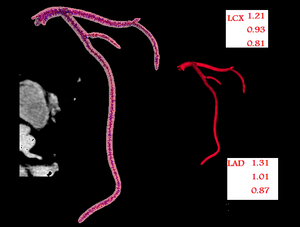

- 8.1 Application of Vascular Model Toolkit (VMTK) for Coronary Arteries